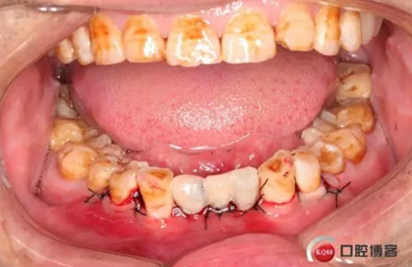

患者,男性,47歲,全身情況良好,無手術禁忌,口內(nèi)因下前牙缺損松動不美觀來院。初診檢查時發(fā)現(xiàn)患者前牙深覆合,下頜32、42缺失。31、41松動二度,切緣磨耗嚴重,可探及髓腔,無保留價值。X-RAY檢查顯示:下頜前牙區(qū)寬度狹窄,咬合空間不足,無法行常規(guī)種植修復.

下圖是術前資料